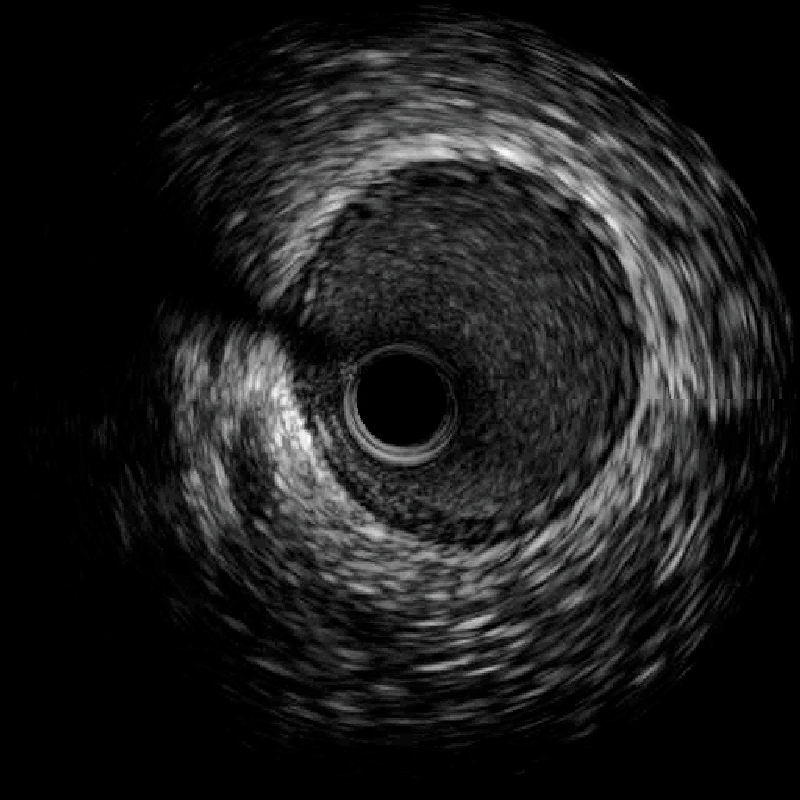

在惠州市中心人民醫(yī)院派駐博羅分院專家、博羅分院心血管內(nèi)科謝桂庭主任和謝志恒科副主任的帶領下,成功開展了博羅分院第一例冠狀動脈血管內(nèi)超聲(IVUS)檢查。術中行冠狀動脈血管內(nèi)超聲(IVUS)檢查:回旋支中段瘤樣擴張,少量血栓影,最大管腔直徑約6mm,未見夾層、血腫(圖4、5)。患者病變?yōu)楣诿}瘤樣擴張并血栓形成,予抗栓等治療后患者好轉(zhuǎn)出院。

文章配圖

(圖5)